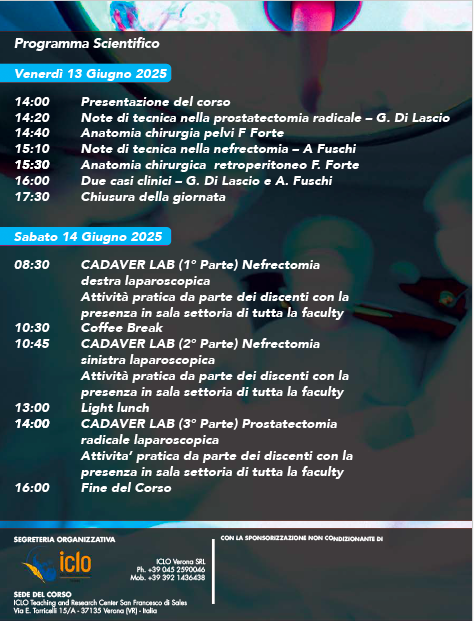

New Edition Verona 13-14 June 2025 Cadaverlab Hands On in Laparoscopic Urological Surgery for the School of Residency in Urology, Sapienza University of Rome. Surgical procedures for radical nephrectomy and radical prostatectomy trainees. Sapienza Policlinico Umberto I European Association of Urology (EAU)

5th Cadaverlab hands on Laparoscopic surgery SAPIENZA UNIVERSITÀ Urologic Residency School ROME. Procedures performed by Residents III IV year: radical nefrectomy - radical prostatectomy. Focus on surgical anatomy and Laparoscopic steps in Major surgery. Sapienza Università di Roma